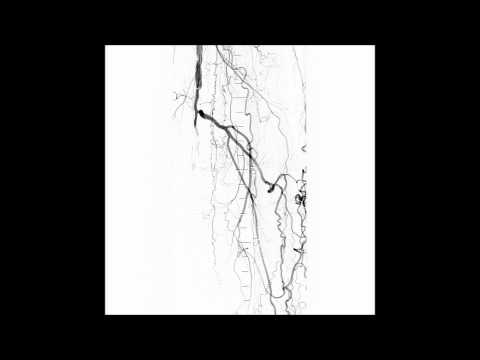

SFA CTO Antegrade and Retrograde Access for Crossing & Treatment